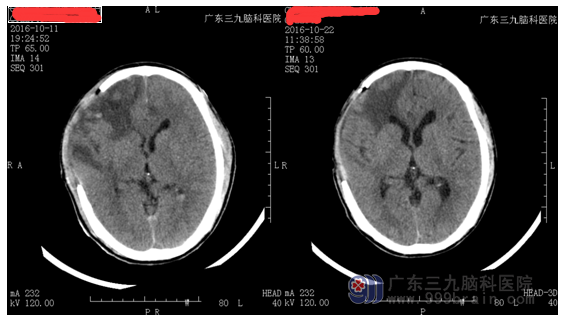

陈某,男,40岁,从高处坠落,致伤头部,伤后出现意识不清、呼之不应,急送当地医院就诊,行颅脑CT示:弥漫性轴索损伤;外伤性蛛网膜下出血;多发脑挫裂伤并脑内血肿形成;于当期行“右侧额颞顶部去骨瓣减压术”,术后患者出现发热、痰多及嘴角抽搐,随后行气管切开术,现患者呈昏迷状,为求进一步治疗,转入我院就诊。

入院后,对患者做辅助检查及康复评估。一、临床诊断及影像检查:重型闭合性颅脑损伤(术后)1.弥漫性轴索损伤2.多发脑挫裂伤并血肿形成3.右侧额颞顶部颅骨缺损4.外伤性癫痫5.肺部感染。二、评估结果:1.意识状态:GCS=6分,重度损伤;PVS评分:1/20分;刺痛有屈伸反应、眼球运动、无听觉反应、疼痛致异常姿势、无语言反应、无交流。2、运动功能:四肢肢体无明显自主运动。3、肌力评分:不能配合。4、其他:留置胃管及尿管、气管切开术后(不能言语);右侧肩关节脱位。存在问题:1、功能障碍:昏迷、四肢运动障碍、吞咽障碍、语言障碍。2、能力障碍:生活完全需要帮助3、参与障碍:无任何参与能力。针对以上情况,予以加强脱水、抗感染、纠正电解质紊乱、高压氧治疗,肠内外营养支持治疗,改善微循环,康复理疗等综合对症有效治疗,患者转危为安,意识恢复清醒,病情逐步转好,无头晕,头痛及肢体抽搐,心肺未见异常,肌张力正常,精神反应良好。出院后复诊情况良好。